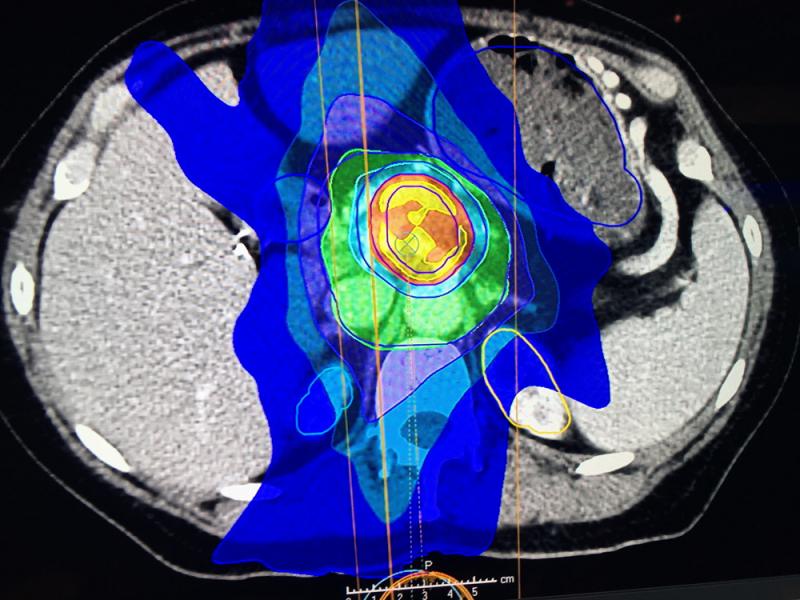

Varian received FDA clearance for its Ethos therapy in February 2020, shown here displayed for the first time at ASTRO 2019. It is an adaptive intelligence solution that uses onboard AI in the treatment system to take the cone beam CT imaging on the system, compare it to the treatment plan and deliver an entire adaptive treatment plan in a typical 15-minute treatment time slot, from patient setup through treatment delivery.

Varian received FDA clearance for its Ethos AI-driven radiation therapy system in February 2020. It is an adaptive intelligence solution that uses AI in the treatment system to take the onboard cone beam CT imaging and compare it to the treatment plan and deliver an entire adaptive treatment plan in a typical 15-minute treatment time slot, from patient setup through treatment delivery.

Tumors change position and size during a course of radiotherapy treatments. Changes in anatomical positioning that move tumors outside TPS margins also occur due to weight loss, position of the uterus, how full the bladder is, and intestinal gas, explained David Sjostrom, Ph.D., deputy chief physicist, Herlev Hospital, Department of Oncology, Division of Radiotherapy, Herlev, Denmark. He had the first clinical experience treating patients with the Varian Ethos system in September 2019.

"Normally it would take days to modify a treatment plan, and you don't do that online with the patient on the table. What we have done up until today was treating within the margins of the plan, or maybe had a study where we had different selections of plans, but it is still not the optimal way of doing it," Sjostrom said.

"So you would have a plan for a small bladder, a medium sized bladder and a large bladder, but what if it is anything in between? With the AI drive workflow, we now get results where we don't need to edit anything and that is the beauty," he explained.

Sjostrom said the system takes a couple minutes to create the plan and then it can be compared to the original plan and you can tell the system which one you want to use, or you can modify one of the plans. However, Sjostrom said so far they have picked the AI generated plan without modification. He said they have averaged a 40 percent reduction in the target margins using the AI-based system.